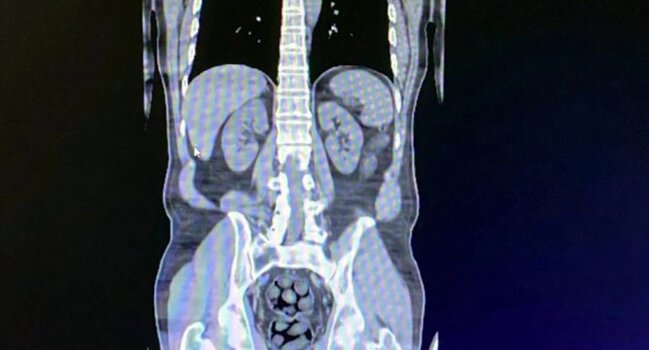

Türkiyədə 3 iranlının mədə və bağırsaqlarından 91 paket narkotik çıxdıTürkiyənin Bitlis vilayətində sərnişin avtobusunda saxlanılan 3 iranlı şübhəlinin mədə və bağırsaqlarında narkotik vasitə gəzdirdiyi müəyyən edilib.

Sonxeber.az "Haber Global"a istinadən xəbər verir ki, şübhəlilərin daxili orqanlarından 91 paketdə 1 kilo 126 qram metamfetamin çıxarılıb.

Hər üç şəxs tibbi əməliyyatdan sonra həbs olunub.